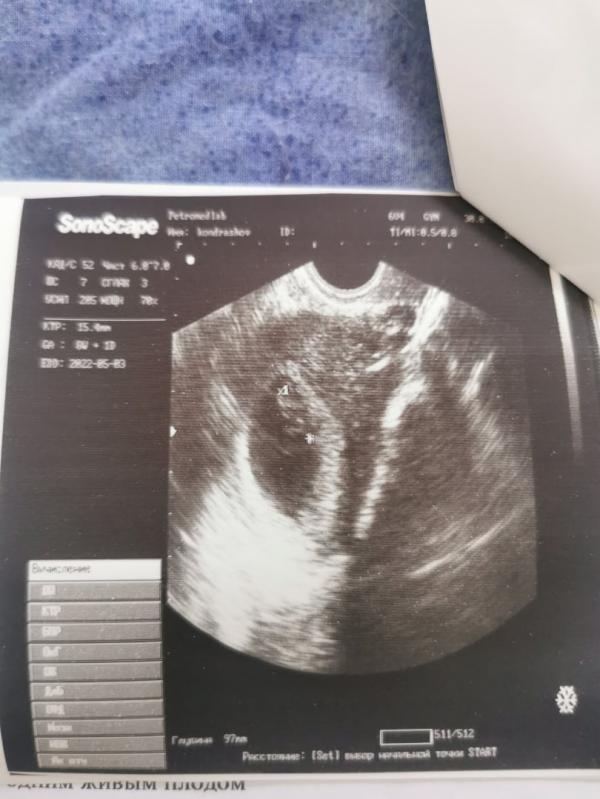

А у нас сегодня было первое УЗИ🖤

Знаете что люблю на таких вот первых фото ребёнка? Что ничего не видно и не понятно 😂

Наша маленькая малинка развивается в соответствии с нормой 💫